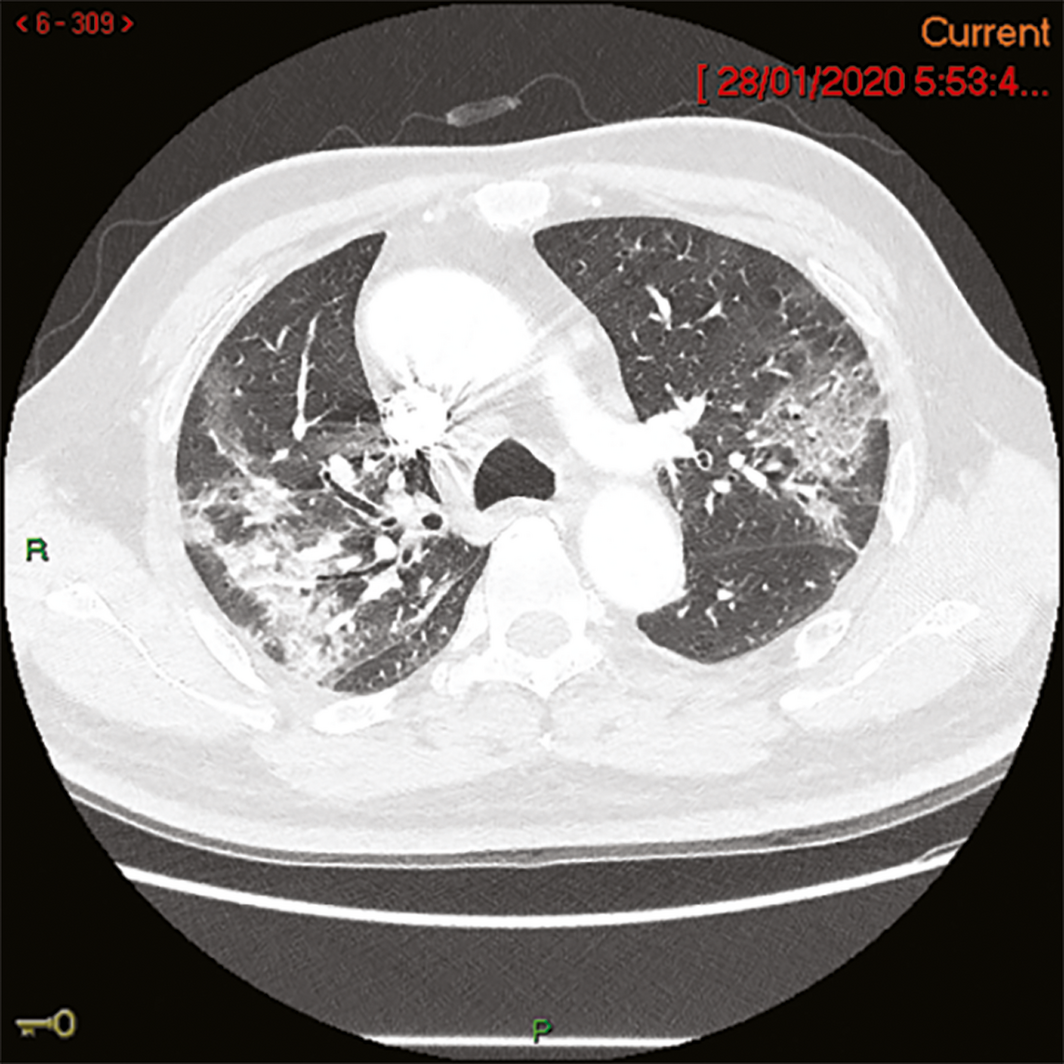

A 58‐year‐old man from Wuhan, China, felt unwell on the day of his arrival in Melbourne (19 January 2020). In China, he had had no contact with live food markets, people known to have COVID‐19, or hospitals. His medical history included type 2 diabetes mellitus, and he had ceased smoking four years previously. He developed fever on 20 January and a cough with sputum production on 23 January; on 24 January, he was admitted to the Monash Medical Centre, Melbourne, from its emergency department with progressive dyspnoea. His temperature was 38.1°C, his heart rate 95 beats/min, and O2 saturation 94% on room air. A chest x‐ray showed subtle ill‐defined opacities in the middle zones bilaterally and in the left lower zone. A thoracic computed tomography scan on admission day four identified extensive ground glass opacities with a peribronchovascular and peripheral distribution in the middle to upper zones of the lungs (Box 1). Full blood examination results included a lymphocyte count of 0.80 × 109/L (reference range, 1.0–4.0 × 109/L). C‐reactive protein concentration peaked on admission day 6 at 182 mg/L (reference range, 0–5 mg/L). Liver function test abnormalities peaked on admission day 12 — alkaline phosphatase, 210 U/L (reference range, 30–110 U/L); γ‐glutamyltransferase, 416 U/L (reference range, 30–110 U/L); alanine aminotransferase, 183 U/L (reference range, 5–40 U/L) — and hepatic steatosis was evident on liver ultrasound. Intravenous ceftriaxone (2 g/day) and azithromycin (500 mg/day) were commenced on admission day 4 to treat potential secondary bacterial pneumonia, although no bacterial pathogen was identified. Low‐flow oxygen (maximum 3 L/min via nasal prongs) was administered until admission day 10. The patient gradually improved; fever, productive cough and dyspnoea resolved by admission day 12, and he was discharged from hospital on 7 February (admission day 15).